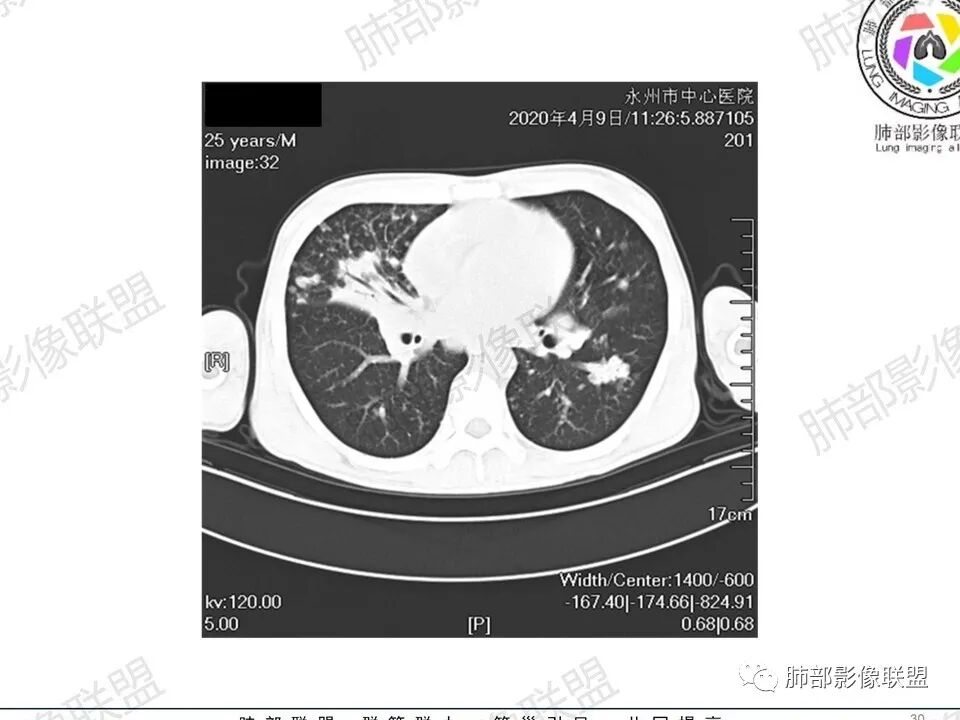

3、影像表现:双肺散在斑片影及结节影,部分结节内可见血管穿行,斑片影沿支气管血管束分布,近胸膜侧病变收缩不明显。部分中央淋巴间质增厚,小叶间隔增厚。病灶内支气管穿行,部分支气管略扩张。局部小结节呈串珠样改变。纵隔、肺门区、锁骨上及腋窝淋淋巴结肿大,部分有融合。心腔低密度。脾大。

2.双肺多发片影及结节影,边界可分辨,右肺中上叶较为密集,没有胸膜下分布优势。病灶实性密度为主,未见钙化及液化。

3.右肺较多微小结节,密度较为浅淡,部分沿血管束分布,未见沿小叶间隔及叶间裂分布结节影,未见典型的终末气道树芽。

4.病灶区域穿行支气管显示良好,未见壁增厚及管腔狭窄。

5.双肺门及纵隔淋巴结显著增大,这改变相当显眼。这里强调“双肺门”及“多发”!

淋巴瘤肺部浸润表现多样,多发结节影是其最常出现的影像学改变,尤其是霍奇金病。

2.右肺多发微小结节影,部分沿血管束分布,尽管未见小叶间隔改变,但双肺门淋巴结增大确实应当首先排除结节病,但经验上说,结节病的增大淋巴结密度往往较高、较密实,边界往往清楚,“独立性”很强,绝无“融合之嫌”!此外,较少出现贫血、脾大,临床表现也往往较轻微。

3.双肺多发结节影,没有明显的新旧不等,没有钙化,微小结节影密度偏低,边缘不够僵硬锐利;病灶区域穿行支气管显示良好,未见壁增厚及管腔狭窄,加之病灶如此广泛,病灶未见收缩、肺叶体积未见缩小,结核中毒症状不明显等等都不支持结核。